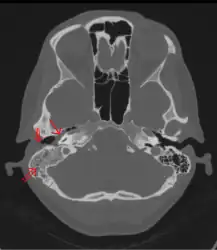

CT scan: Otitis media (simple arrow) and mastoiditis (double arrow) of the right side (left side in image). The external auditory canal is partially occupied by suppuration (triple arrow). 44-year-old woman